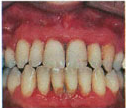

Stage 2

Mild gingivitis caused by plaque and calculus manifested as red gums,tender on touch and ready to bleed.

Stage 3

Periodontitis caused because of retained calculus manifested as gingival recession and pocket formation. Bone levels are also affected.